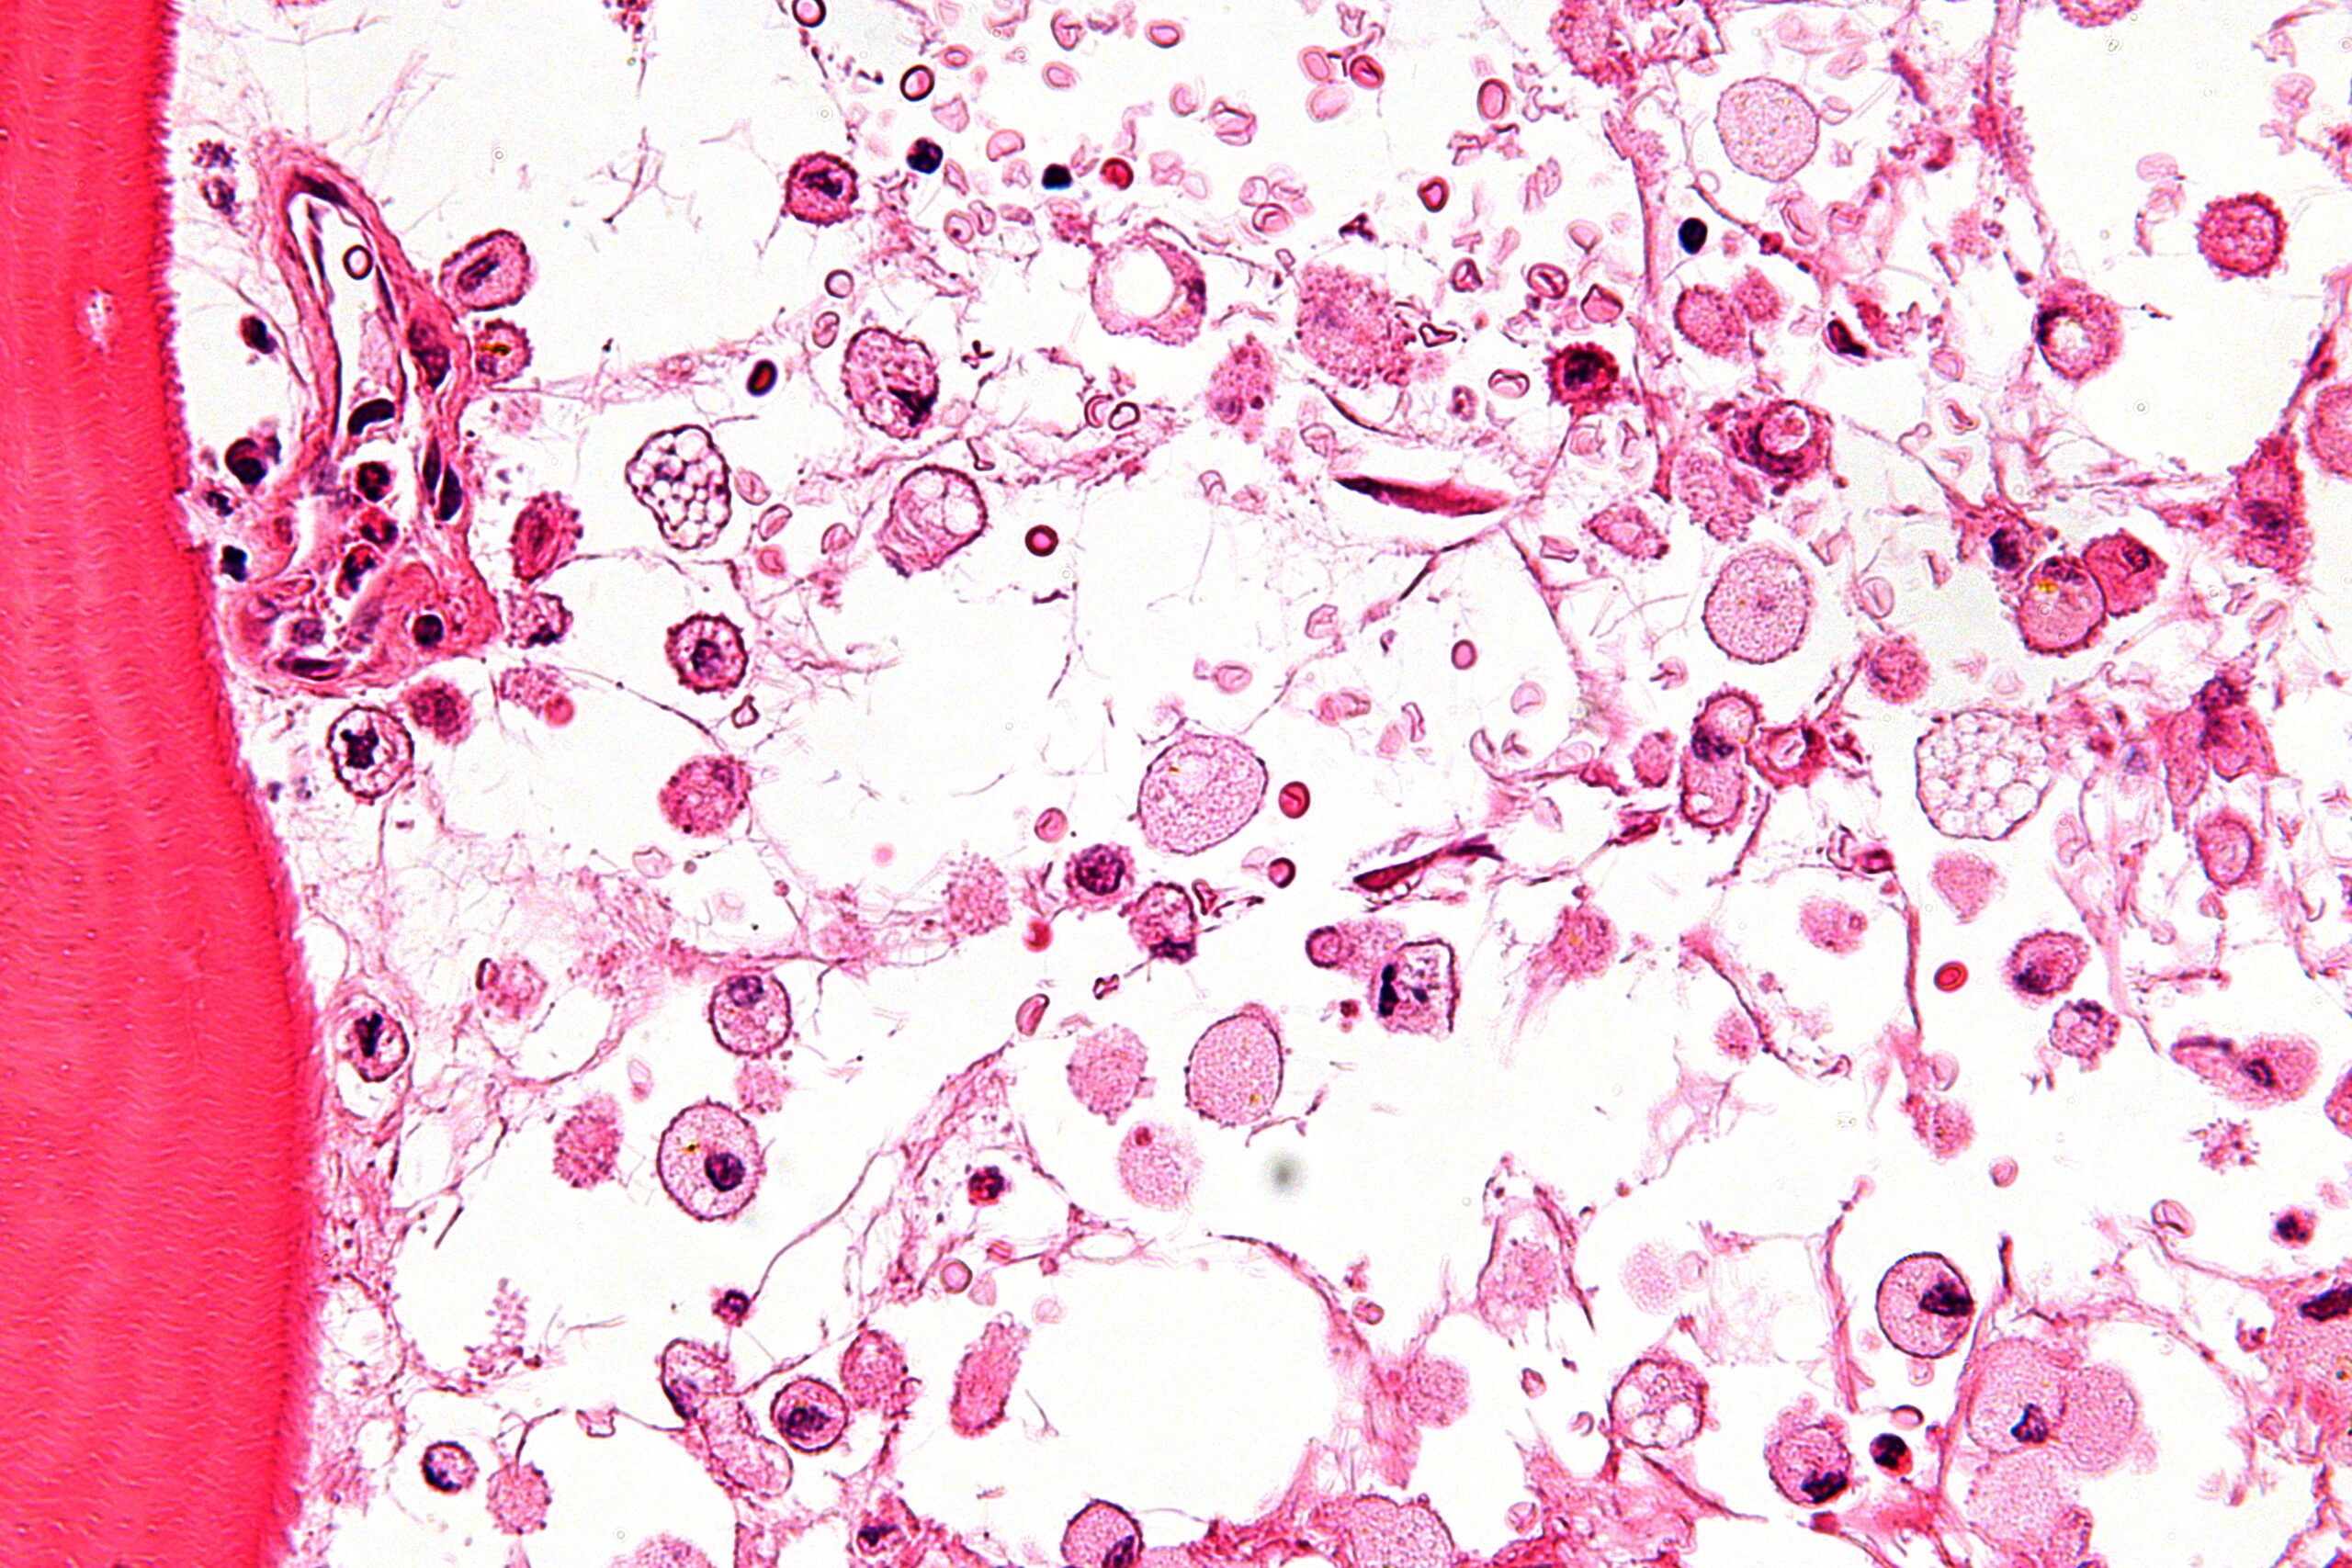

Macrophages in bone marrow affected by Gaucher’s disease (Nepron, CC BY-SA 3.0)

In some disease, the body cannot make specific enzymes. The lack of these enzymes can cause severe symptoms of disease and even in some cases death. For example, Gaucher’s disease is a genetic disease where the body does not make the enzyme glucocerebrosidase. This enzyme breaks down glucosyceramide, a component of the cell membrane in the removal of cells that are worn out or damaged in some way. As a result there is a build-up of glucosyceramide in organs including the spleen, liver, lungs, brain and bone marrow. It causes an enlarged liver and spleen and many metabolic problems. Children who inherit the most severe form of the disease often do not live beyond the age of two.

The most common form of Gaucher’s disease affects about one in every 40,000 live births in the US. In recent years new drugs such as velaglucerase alfa have been developed. They are produced using recombinant DNA technology (genetic engineering) of bacteria. The drugs are expensive and an affected person has to take the drug for life, but it effectively replaces the missing enzyme and allows them to live a normal life.